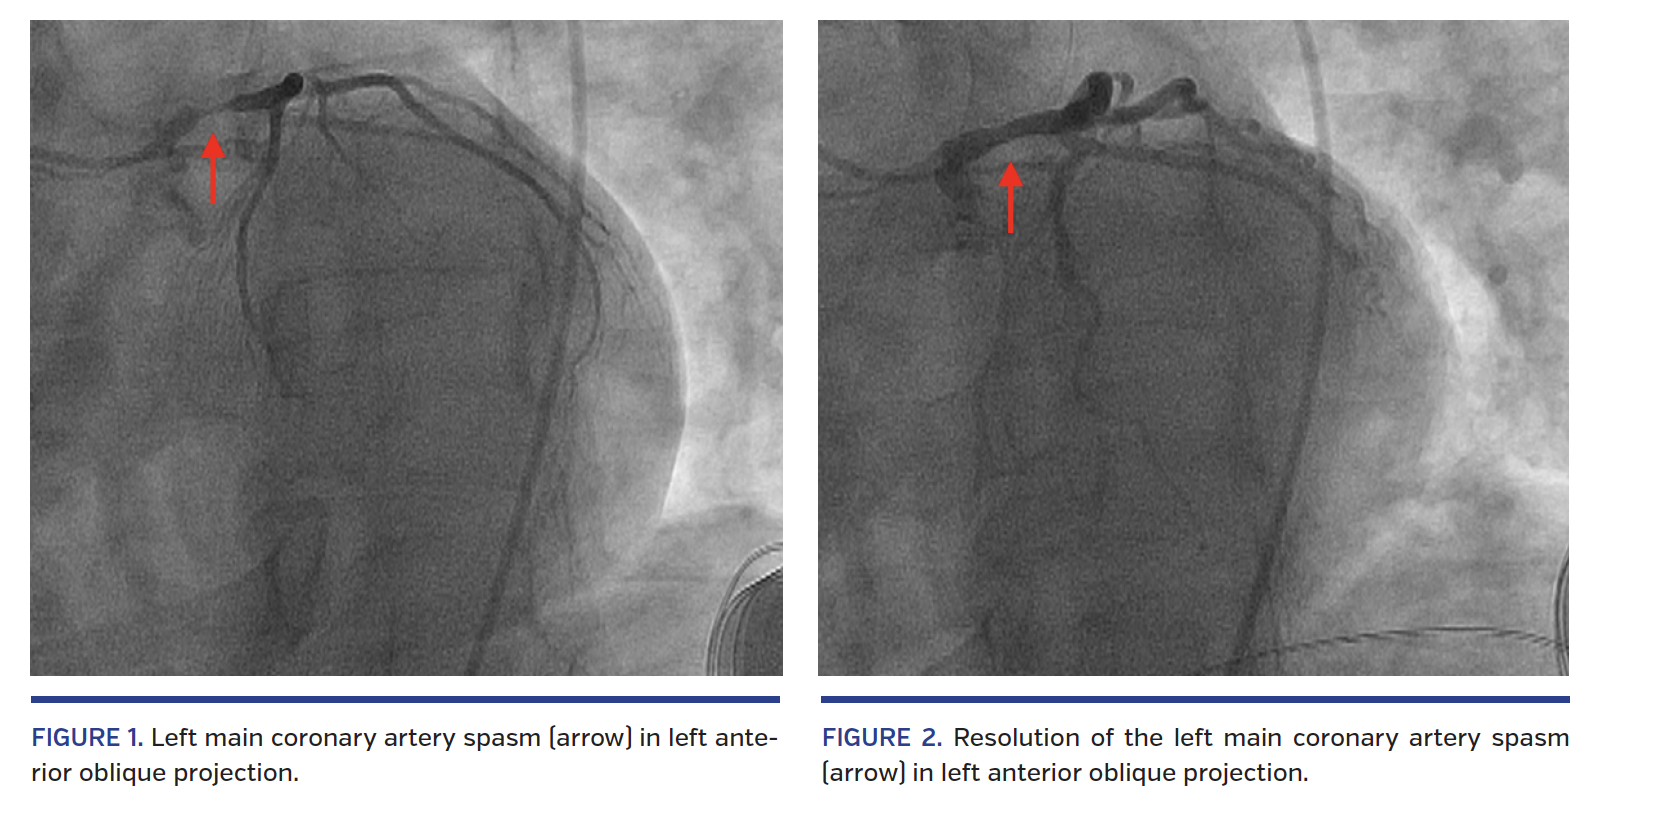

A 44-year-old man presented with typical angina. He previously received a subcutaneous implantable cardioverter defibrillator after a cardiac arrest episode several years ago in another facility. Nuclear myocardial perfusion stress test demonstrated reversible anterolateral ischemia. Upon engagement of the left main (LM) coronary artery with a JL4 catheter, the patient developed chest pain with ST elevations and severe LM stenosis was observed (Figure 1; Video 1). A total of 400 µg intracoronary nitroglycerin were administered. The patient’s chest pain and ST elevations resolved. Repeat angiography demonstrated almost complete resolution of LM spasm (Figure 2; Video 2). No other significant coronary artery disease was found.